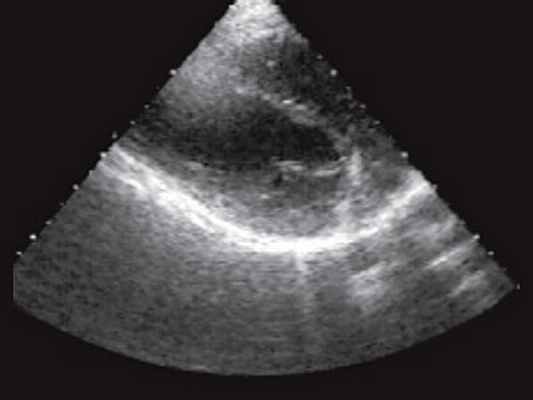

При неизмененной слизистой оболочке прямой кишки и наличии опухолевидного образования в толще ее стенки, кроме лимфосаркомы следует думать о такой патологии, как лейомиосаркома, липома, ангиома, гемангиоэпителиома прямой кишки, воспалительные заболевания. Для липом и сосудистых опухолей характерна более высокая эхогенность, чем при лимфосаркоме. Для лейомиосаркомы характерна низкая эхогенность, но более четкие и ровные контуры [20]. Острые парапроктиты (рис. 3) в стадии инфильтрации имеют более высокую эхогенность и звукопроводимость, неоднородную внутреннюю структуру, а после формирования капсулы они становятся практически анэхогенными, четко отграниченными от окружающих тканей.

Рис. 3. Задний подковообразный острый парапроктит. В отличие от лимфосаркомы имеются четкие контуры образования, расположенного кзади от стенок прямой кишки, хорошо видны плотные стенки, дистальное усиление эхосигнала.